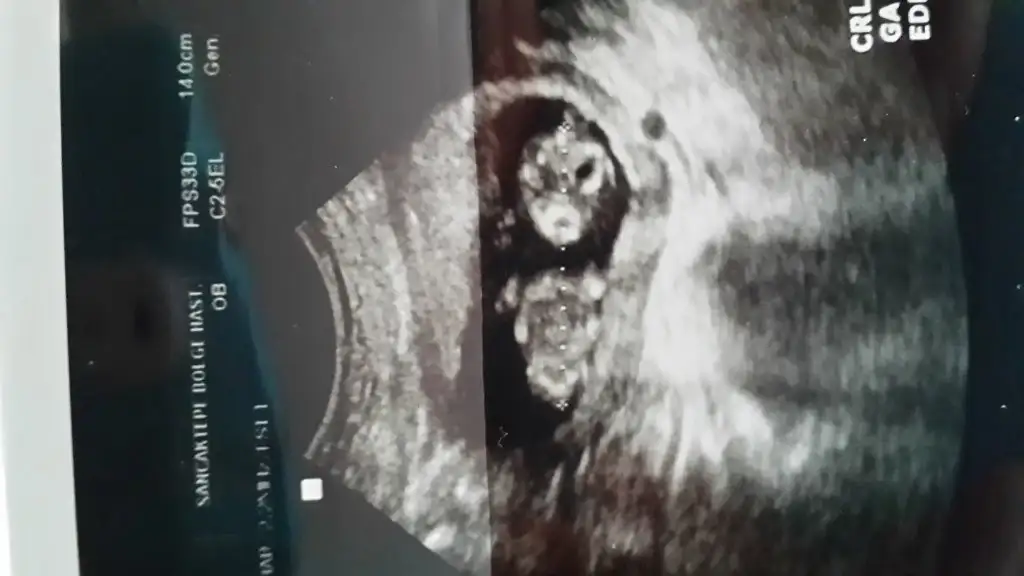

Bu haftada kac haftalik canim en basindan beri ben kiz demistim şimdiki fikrinde ayni cikinti paralel diğer görüntüde ki cikinti başka bizi pipi o kadar kicuk olmaz çünkü benceYorum bekliyorum lütfen.

Atropin sana Nasil erkek dediler ya ben hala pipi göremiyorum acaba kordon filanlami karistrdilar seninbebisin nubu bariz paraledi bbuda gitsene Dr bence sende yanildilar hissediyprumkızlarrr tekrar merhaba 2-3 hafta öncesinde bebeğimin fotoğraflarını yüklemiştim ve epeyce bir kız olucak yorumunu almıştım. geçen perşembe doktora gittim. kendi doktorum cinsiyet sölemediği için başka bir doktora gittim. veeeee cinsiyet yorumu "ERKEK" ama nedense kız gibi geliyor bana. sizlere zahmet tekrar bi baksanız bi yorum yapsanız şimdiden sağolun.....

13 haftalik canimHAftasi nedir

Prensesin olacak bence canm13 haftalik canim